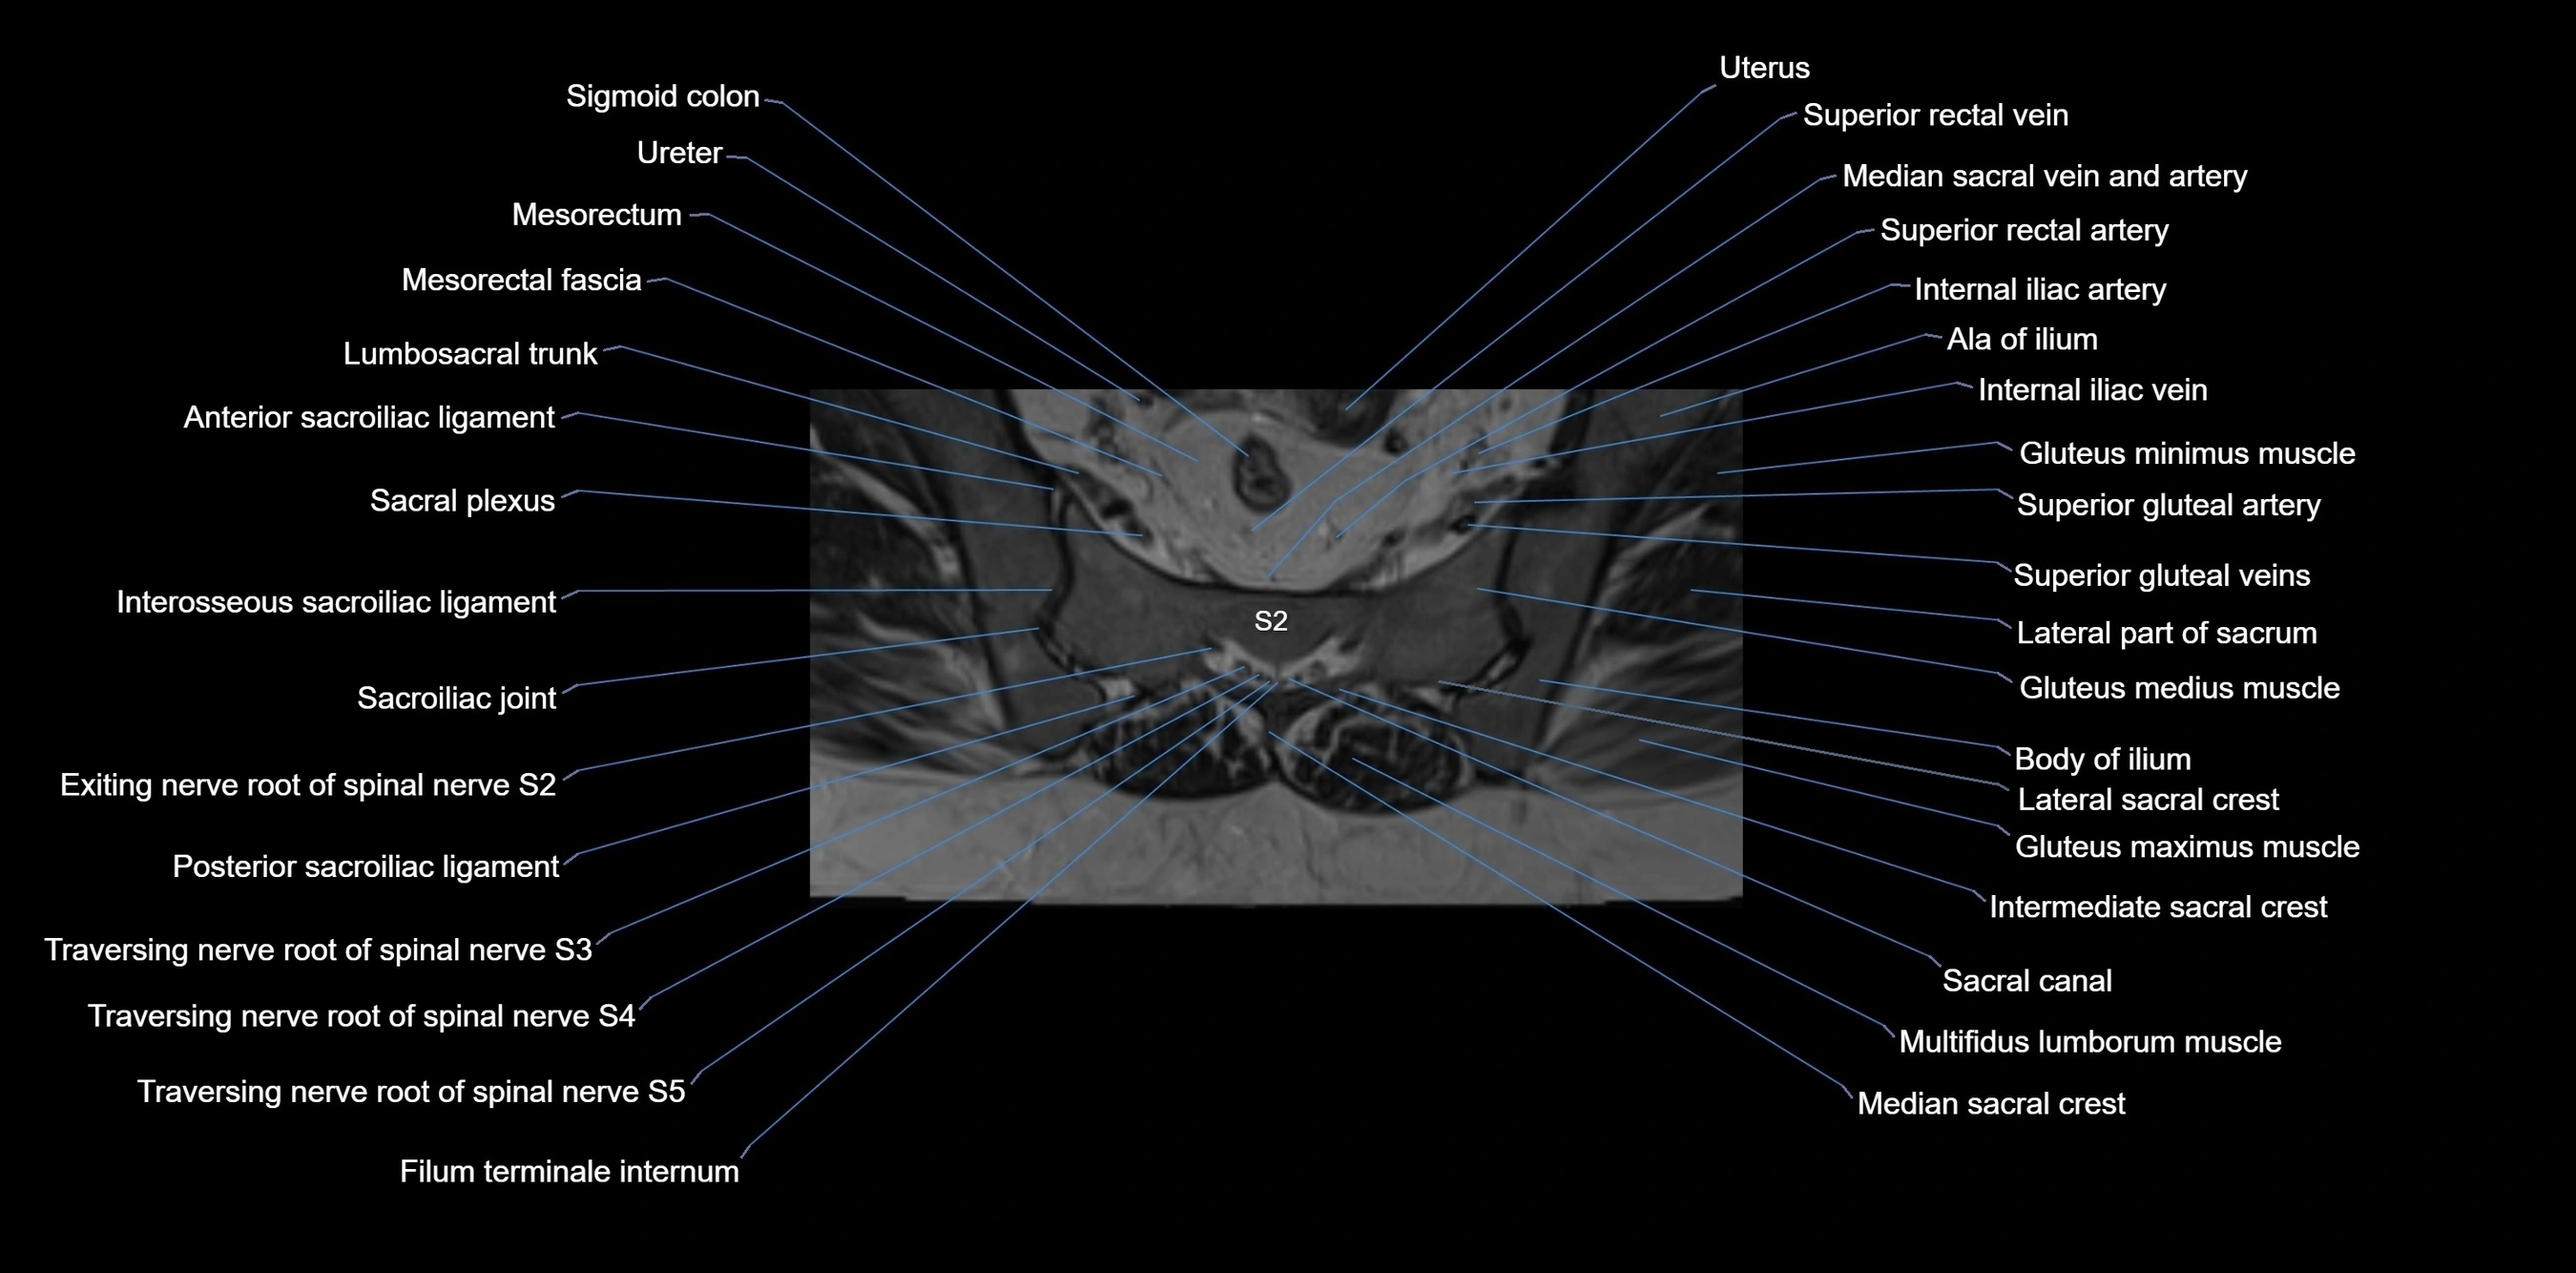

MRI image

image